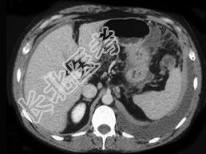

- 单项选择题女,36岁, 低热、乏力,腹胀不适1月余, 结合影像检查,应考虑为  (    )

- A、肝硬化腹水

- B、结核性腹膜炎

- C、腹腔转移瘤

- D、心源性腹腔积液

- E、急性化脓性腹膜炎